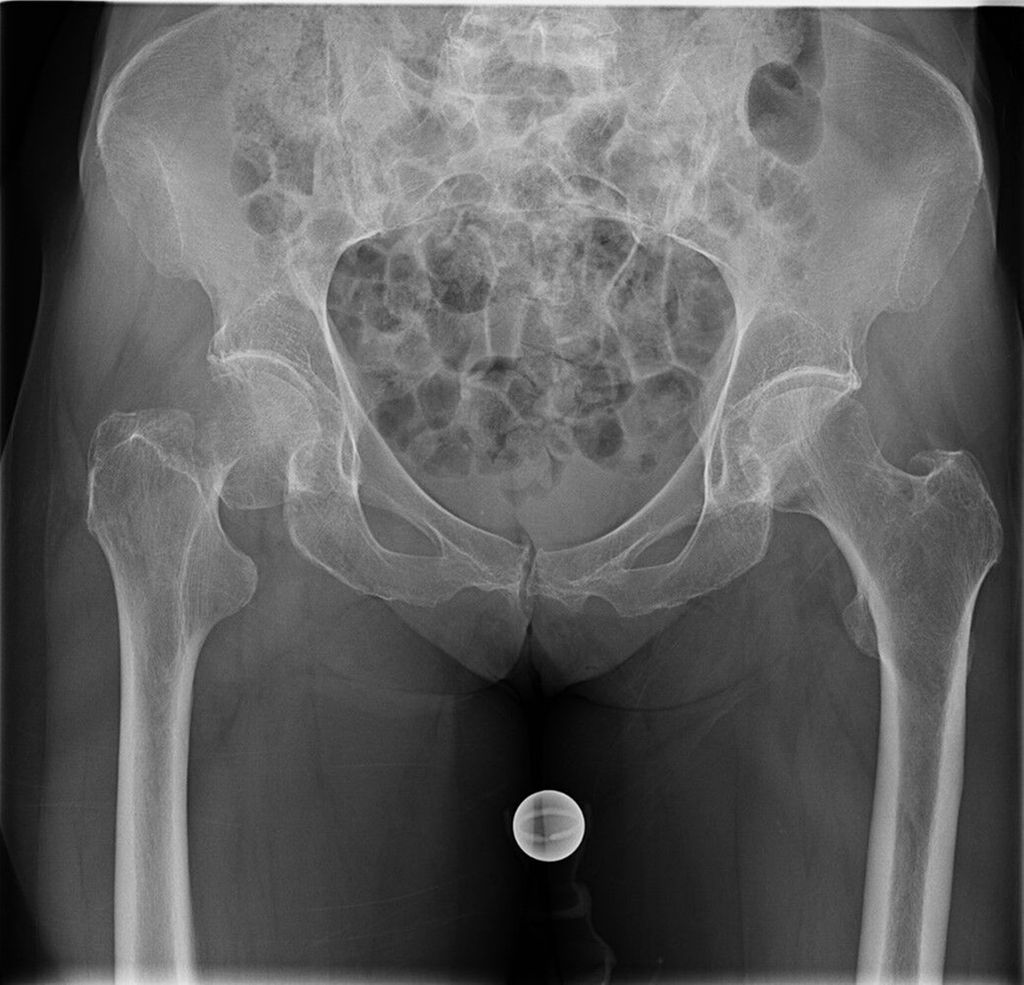

Dorr et al.17,18 entwickelten 1993 eine Einteilung in drei Femurtypen, um röntgenologisch eine Einschätzung der Knochenqualität zu ermöglichen (Abb.1). Der Dorr-Typ A zeigt einen schmalen Diaphysenkanal und wird auch als «Champagnerflöte» bezeichnet. Dieser Typ wird häufiger bei jüngeren, schwereren und männlichen Patienten beobachtet. Der Typ B ist durch eine Reduzierung der medialen und dorsalen Kortikalis gekennzeichnet, was zu einer Verbreiterung des Diaphysenkanals führt. Dieser Femurtyp kommt häufiger bei Männern als bei Frauen vor. Der Dorr-Typ C wird auch als «Ofenrohr» bezeichnet und ist durch einen breiten Kanaldurchmesser charakterisiert, der häufiger bei dünneren, älteren weiblichen Patienten auftritt. Die Inzidenz periprothetischer Frakturen ist bei Patienten mit Dorr-Typ C deutlich erhöht. Gkagkalis et al.19 stellten im Rahmen einer Multicenterstudie fest, dass bei Implantation einer Kurzschaftprothese und Vorliegen eines Dorr-Typs C die Inzidenz einer periprothetischen Fraktur um über 20% erhöht ist.